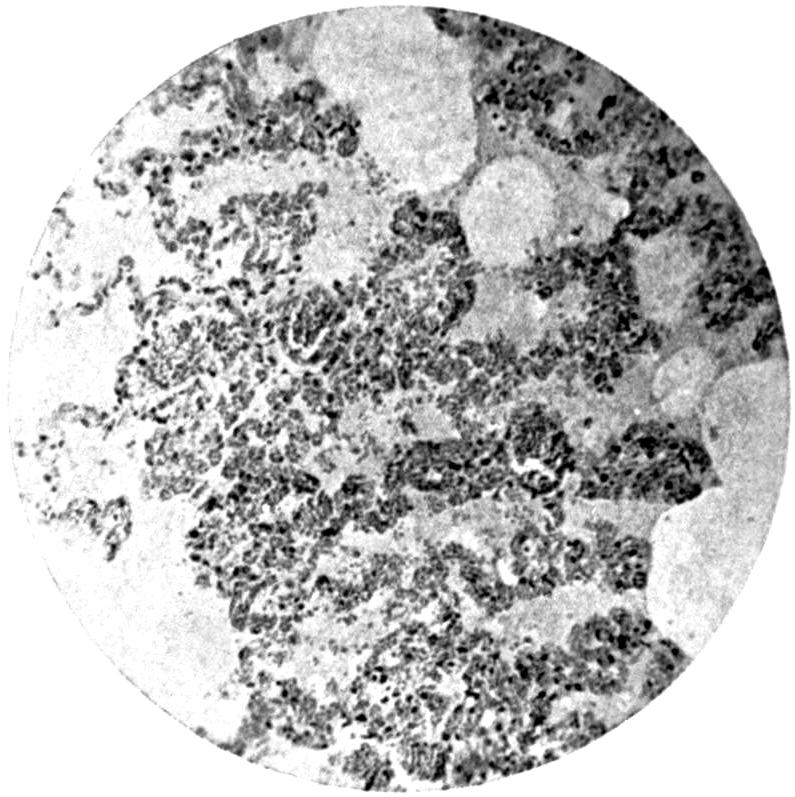

Plate IV. 276